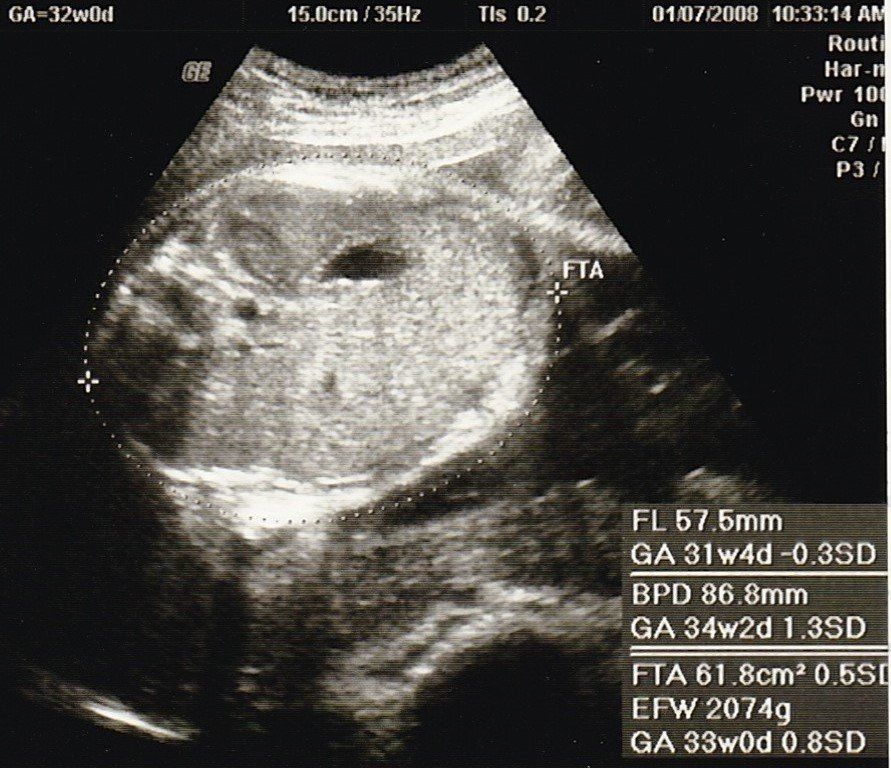

妊娠32週目のエコー写真

2000gを超えました。安心と同時に、体の重い状態がまだあと2カ月も続き、まだ大きくなるのかと思うと少し憂鬱に。体重も7kg以上増え助産師さんに注意されたものの、何か口に入れていないと気持ち悪くなるような状態で、つい食べ過ぎて自己嫌悪になることもありました。